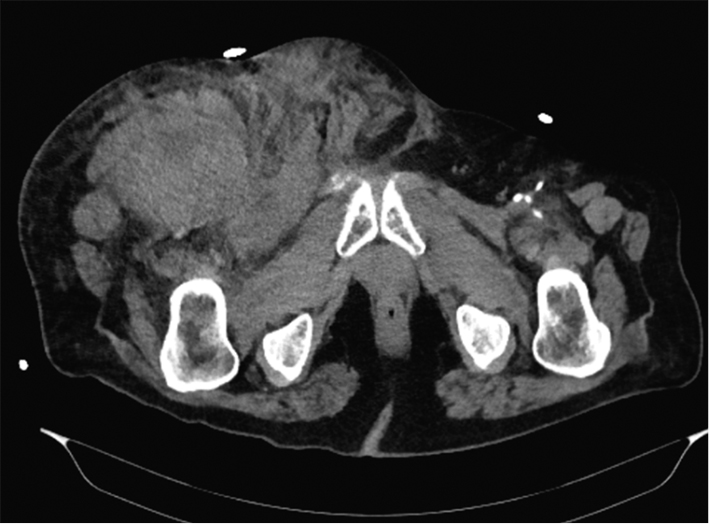

Hematoma of the puncture site is the most common complication, and it has been reported to occur in 5%–23% of cases by different authors. The hematoma scope varies from slight staining of the skin at the puncture site to a massive tumor requiring surgical treatment and blood transfusion. First, the causes of hematoma include multiple puncture attempts, incorrect or insufficiently long-lasting postoperative compression, and incorrect use of suturing devices. In the vast majority of cases, hematomas do not require special treatment and persist for 1–2 weeks. Follow-up and local therapy with heparin ointment are usually sufficient. If a growing hematoma is detected during the intervention itself, it is possible to use endovascular methods of treatment, such as balloon compression or implantation of a short stent or stent prosthesis. In this case, a contralateral approach is required. If it becomes necessary to implant a stent or a stent graft, it should be taken into account that the puncture site is anterior to the hip joint, that is, it is located in the mobile segment. The implantation of a stent in such a segment poses the risk of implant fracture and, as a consequence, the occurrence of vascular obstruction, limiting blood flow. Sometimes surgical treatment is necessary due to the hematoma size. The CT presentation of such a hematoma is shown in Figure 2. In case of the rapid development of a massive hematoma, necrotic changes in soft tissues are also possible. An example of such a case is presented in Figure 3. A special variant of local hematoma leads to the occurrence of a false aneurysm (0.5%–9%), and emergency surgery is indicated in this case.When performing postoperative compression, the size of the tool used to catheterize the vessel should be considered. The compression force should be approximately 20 mmHg above the systemic systolic pressure. The reference points in Table 2 can be used to determine the compression time. When using tools larger than 6 Fr in diameter for arterial access, the use of a suturing device is recommended. In the early postoperative period, strict adherence to bed rest by the patient and control of the puncture site by the department staff are of key importance.

Fig. 3. Massive puncture site hematoma extending to the proximal femur; a ― radiological image; b ― rapid soft tissue necrosis due to hematoma pressure from the inside; c ― clinical presentation 8 days after hematoma evacuation and revision of the puncture site (author’s case)